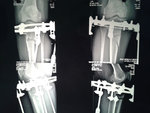

рентген в 90 дней.

Костная мозоль растёт хорошо, планируем снятие аппаратов в 4 месяца.